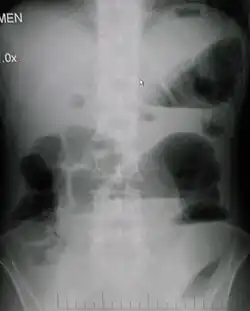

| Upright abdominal X-ray demonstrating a small bowel obstruction. Note multiple air fluid levels. | |

Radiological signs of bowel obstruction include bowel distension (small bowel loops dilated >3 cm) and the presence of multiple (more than 2) air-fluid levels on supine and erect abdominal radiographs.[16] Ultrasounds may be as useful as CT scanning to make the diagnosis.[17]